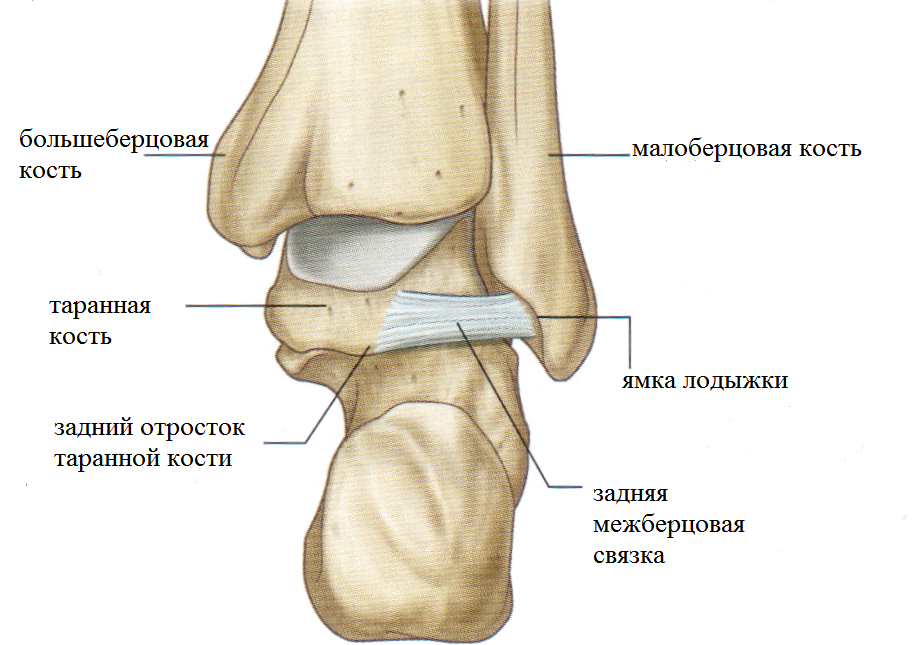

Анатомические фото голеностопного сустава и его суставных поверхностей